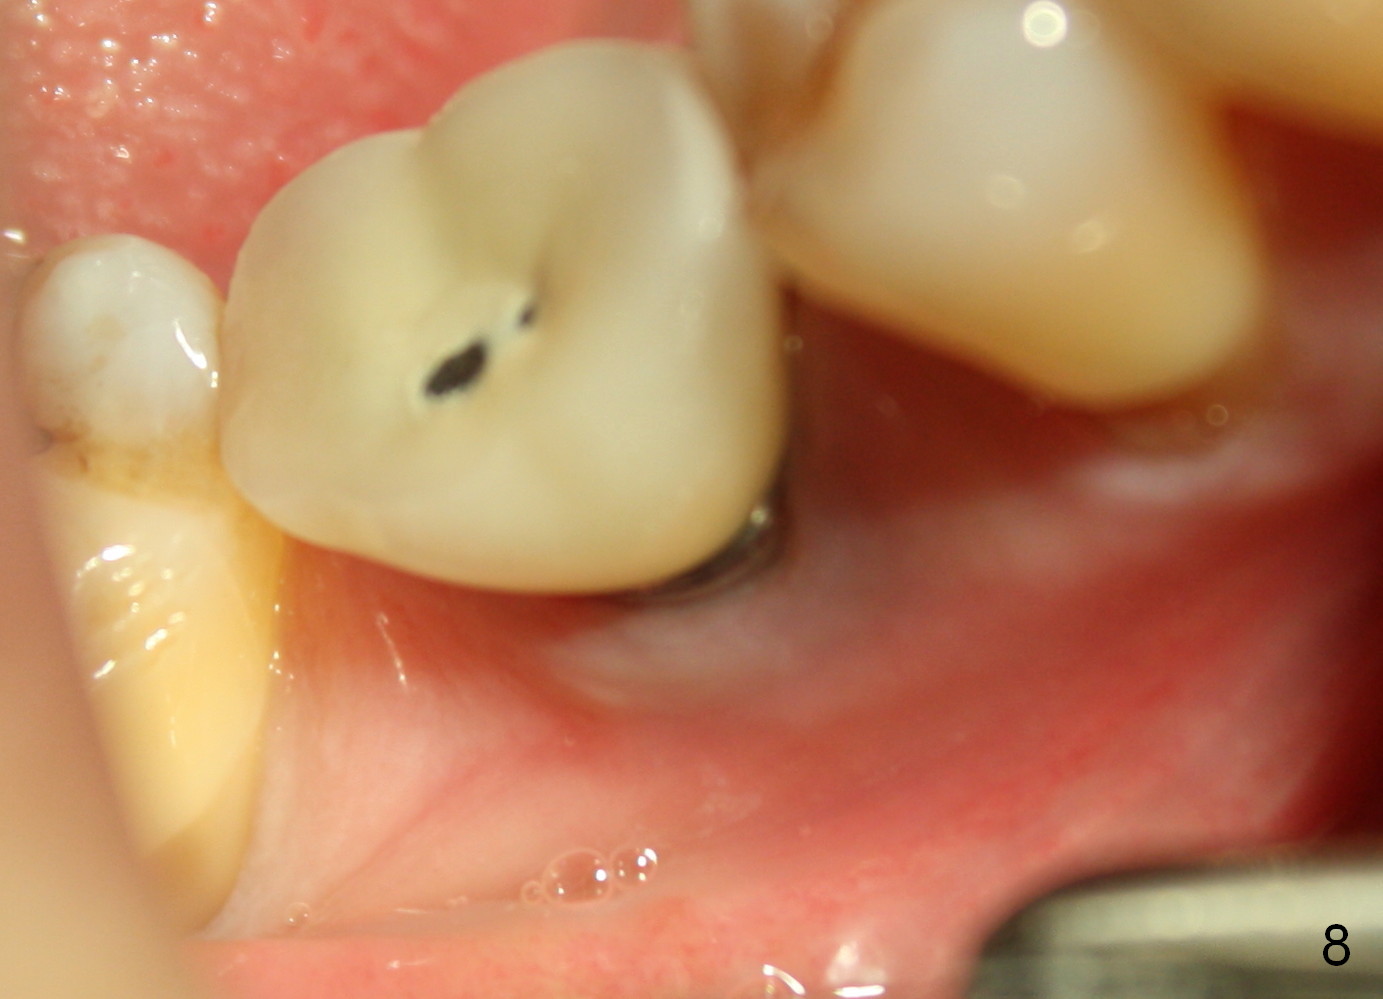

Fig.6-8 show images taken 6, 21 and 34 months post cementation. Bone remains stable 6 years postop (Fig.9).

Metal exposure of the PFM crown (Fig.5,8) is associated with supraeruption of the opposing tooth (Fig.10 arrow). Increased bone density around the coronal portion of the implant 8 years 2 months post cementation (Fig.11 *) suggests bruxism, which is related to distal marginal porcelain chip (^). There is no food impaction with a new crown (Fig.12).